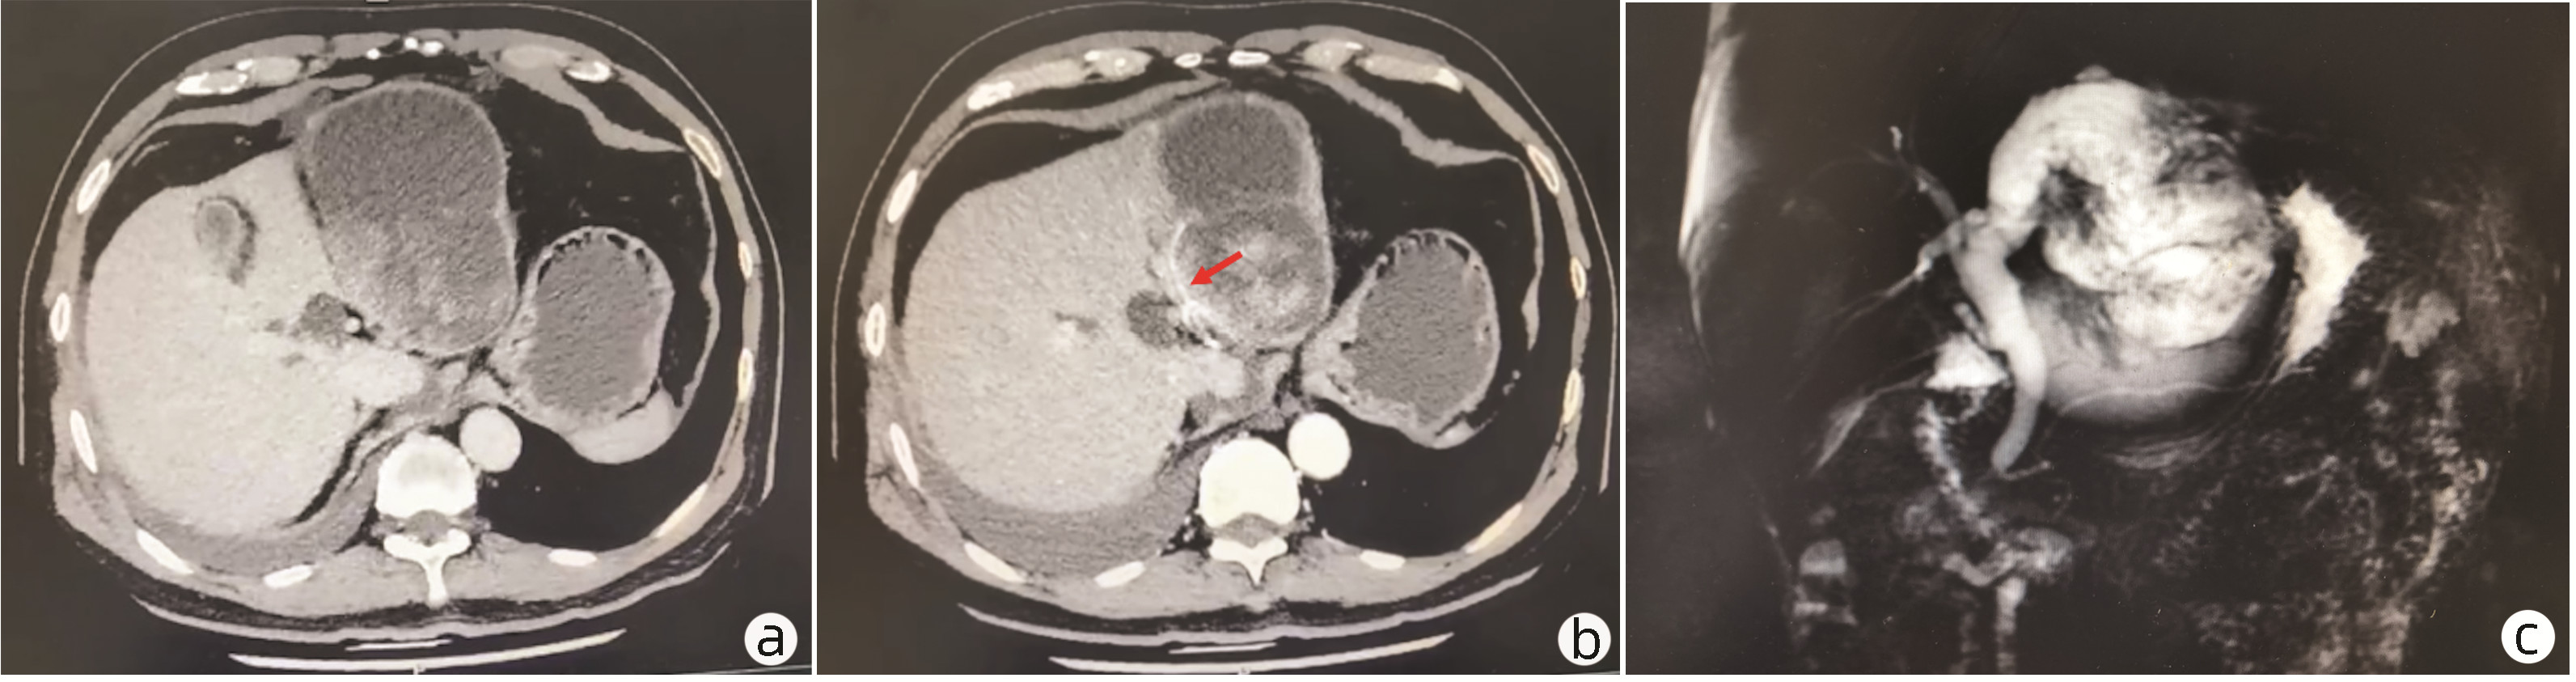

Focal nodular hyperplasia-like nodules in liver cirrhosis: An imaging analysis of three cases

Zinan LI, Shaoshan TANG, Xingni WU, Xiang LI

2023, 39(1): 142-146. DOI: 10.3969/j.issn.1001-5256.2023.01.021

Abstract(2471) HTML (2381) PDF (3394KB)(133)